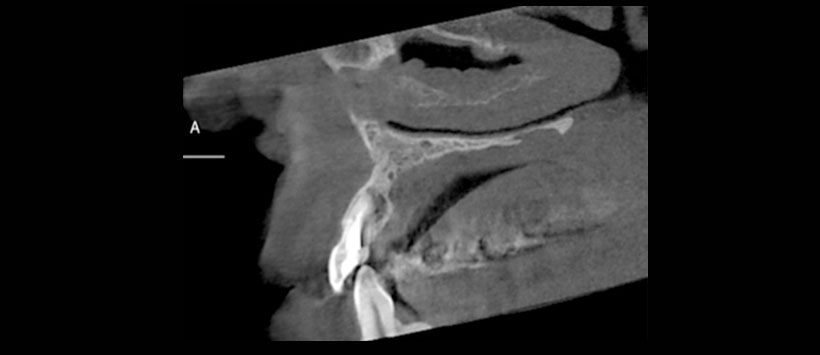

A los tests de sensibilidad, solo es positivo para percu- sión, y es sensible a la palpación periapical. No hay cambios de color coronario, y los exámenes térmicos y eléctricos son negativos. Se solicitan radiografías convencionales, en las que se observa una imagen radiolúcida extensa de lími- tes netos no corticalizada, en relación a piezas 2.1, 2.2 y 2.3. Se complementa con tomografía computarizada Cone Beam (CBCT) (Figura 2), mostrando una imagen compatible con quiste radicular inflamatorio en pieza 2.2. Sus mediciones son 20 mm mesio-distal, 13 mm vestíbulo-palatino y 11 mm céfalo-cauda. Posterior al tratramiento, se le realizo una tomogriafia de control a los 20 meses para evalular el estado del tratamiento endoodntico asi como la cirugia.(Figura 3)

La tomografia volumetrica de haz conico fue la herramienta de elección para evaluar este tipo de casos, debido a que permite evaluar en forma tridimensional la anatomía dentaria, canalicular y ósea, permitiendo determinar el compromiso de tablas óseas, estructuras vecinas (p.ej., piso nasal) y las dimensiones de las lesiones.